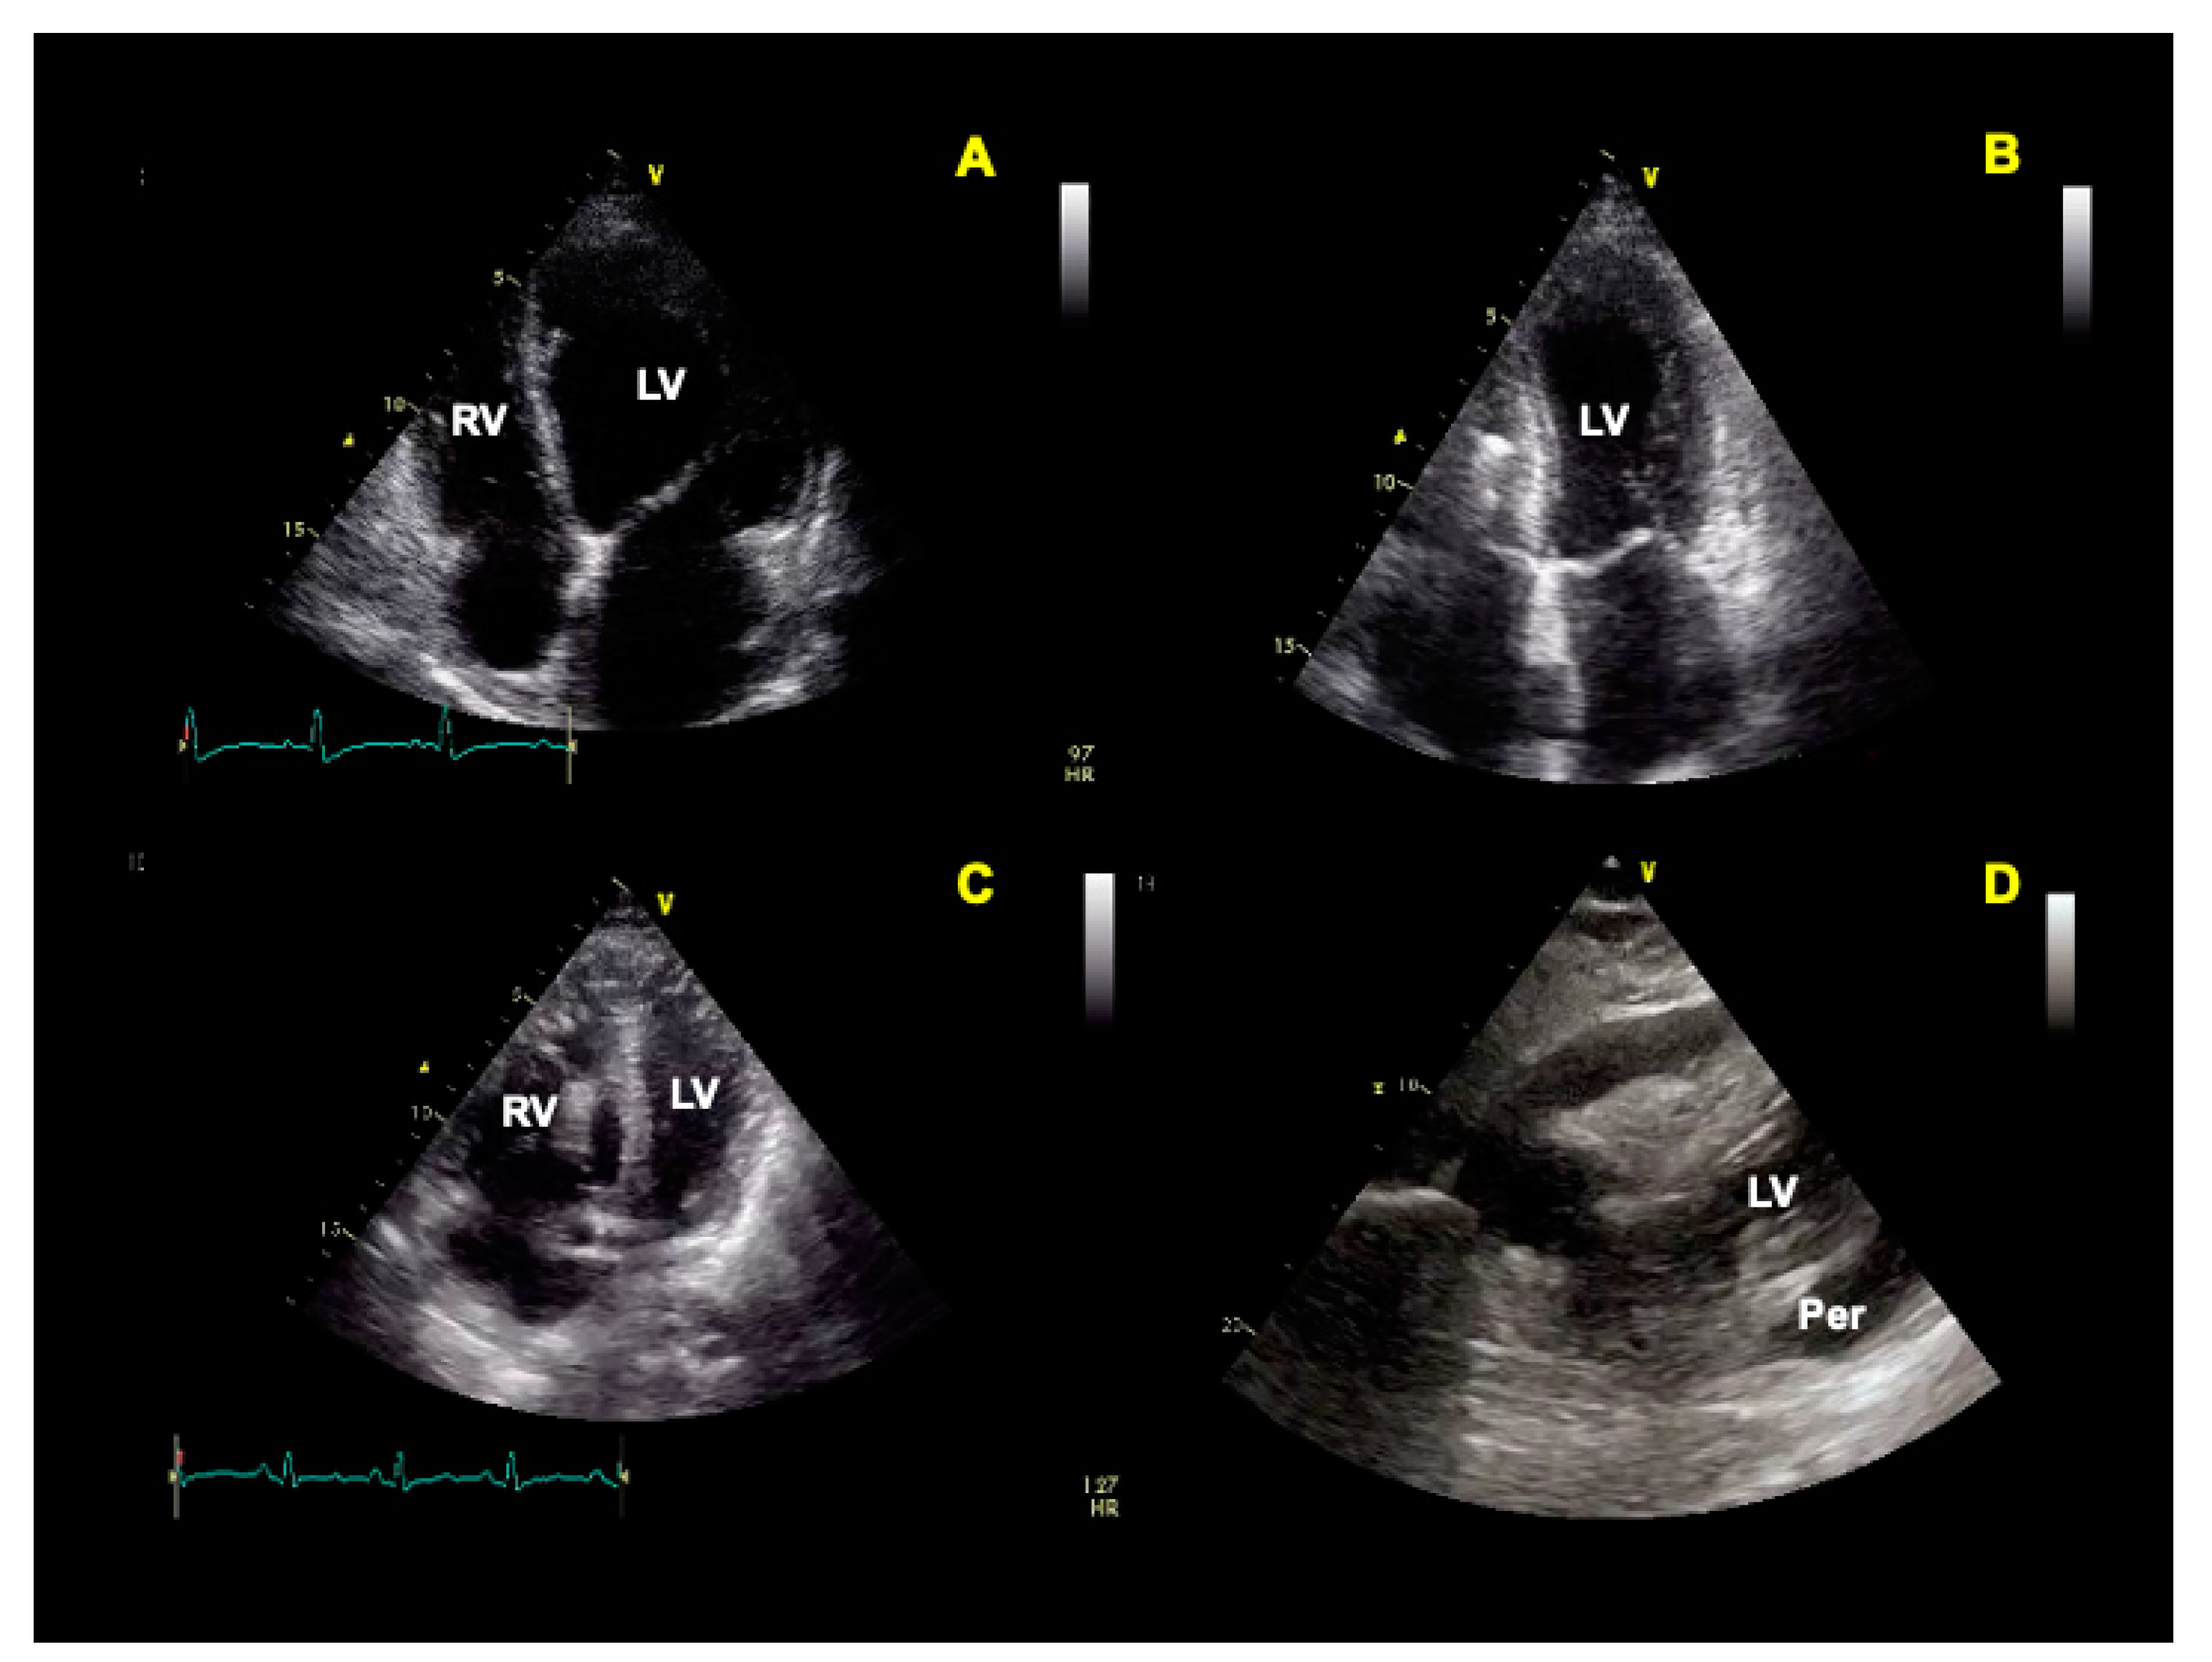

- Carrizales-Sepúlveda, E.F.; Vera-Pineda, R.; Flores-Ramírez, R.; Hernández-Guajardo, D.A.; Pérez-Contreras, E.; Lozano-Ibarra, M.M.; Ordaz-Farías, A. Echocardiographic Manifestations in COVID-19: A Review. Heart Lung Circ. 2021, 30, 1117–1129. [Google Scholar] [CrossRef]

- Cau, R.; Bassareo, P.; Saba, L. Cardiac Involvement in COVID-19—Assessment with Echocardiography and Cardiac Magnetic Resonance Imaging. SN Compr. Clin. Med. 2020, 2, 845–851. [Google Scholar] [CrossRef] [PubMed]

- Citro, R.; Pontone, G.; Bellino, M.; Silverio, A.; Iuliano, G.; Baggiano, A.; Manka, R.; Iesu, S.; Vecchione, C.; Asch, F.M.; et al. Role of multimodality imaging in evaluation of cardiovascular involvement in COVID-19. Trends Cardiovasc. Med. 2020, 31, 8–16. [Google Scholar] [CrossRef] [PubMed]

| Pericardial involvement with effusion |